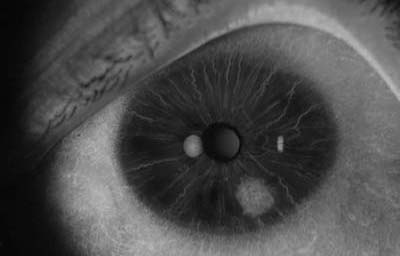

Melanocitomas

Melanocitoma es una lesión benigna, profundamente pigmentada, variante del, nevus uveal que fue originalmente descrito por Zimmerman y Garron en 1962 en el nervio óptico; ahora se sabe que puede aparecer en cualquier lugar del tracto uveal.

Son masas con algo de elevación, con pigmento marrón oscuro casi negro, frecuentemente con apariencia de “ montículo de arena negra”. Sus células son ovoides con núcleos uniformes, pequeños y muy pigmentados. pueden generar satélites en el estroma o en el ángulo de la cámara anterior. Pueden evolucionar a Melanoma (30)

Archivo Fotográfico Dr. Francisco Barraquer. 2012

Archivo Fotográfico Dr. Francisco Barraquer. 2017

Estudio comparativo